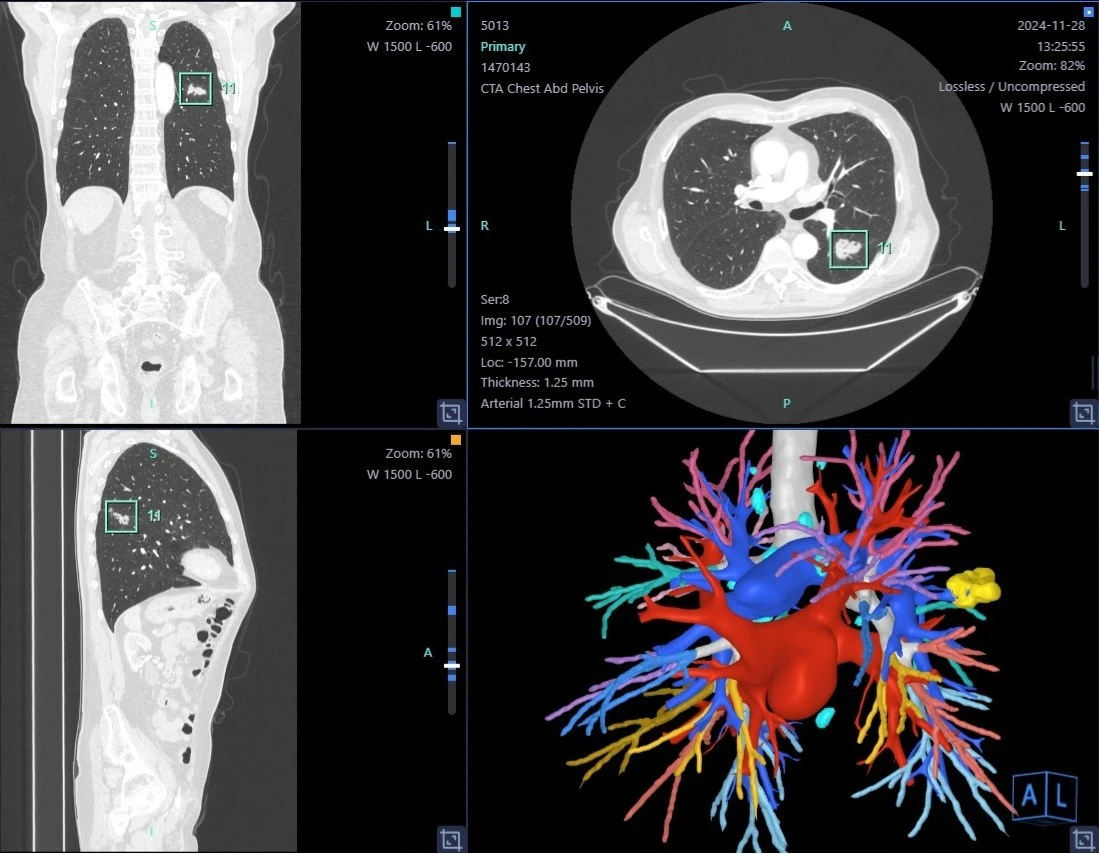

1. Προσχεδιασμός με Τρισδιάστατη CT Απεικόνιση:

• Πραγματοποιείται υψηλής ανάλυσης αξονική τομογραφία θώρακος (CT).

• Τα δεδομένα ανασυντίθενται σε τρισδιάστατο μοντέλο των πνευμονικών δομών, περιλαμβάνοντας αγγεία, βρόγχους και τον όζο.

• Αυτό επιτρέπει τον ακριβή υπολογισμό της θέσης του όζου σε σχέση με ανατομικά ορόσημα (π.χ. αγγεία, λοβοί, βρογχοπνευμονικά τμήματα).

3. Συνδυασμός Δεδομένων σε Πραγματικό Χρόνο:

• Το προεγχειρητικό 3D μοντέλο "συγχωνεύεται" με την διεγχειρητική εικόνα (κάποιες φορές μέσω τεχνολογίας επαυξημένης πραγματικότητας - augmented reality ή λογισμικών πλοήγησης).

• Ο χειρουργός γνωρίζει με μεγάλη ακρίβεια πού βρίσκεται ο όζος ακόμα και αν είναι μη ψηλαφητός.

Η 3D-LUMINA που εφαρμόζεται αποκλειστικά στον Κυανού Σταυρό είναι μια υβριδική τεχνική απεικόνισης που συνδυάζει τρισδιάστατη ανασύνθεση πνευμονικών δομών με φθορίζουσα καθοδήγηση μέσω ινδοκυανίνης.